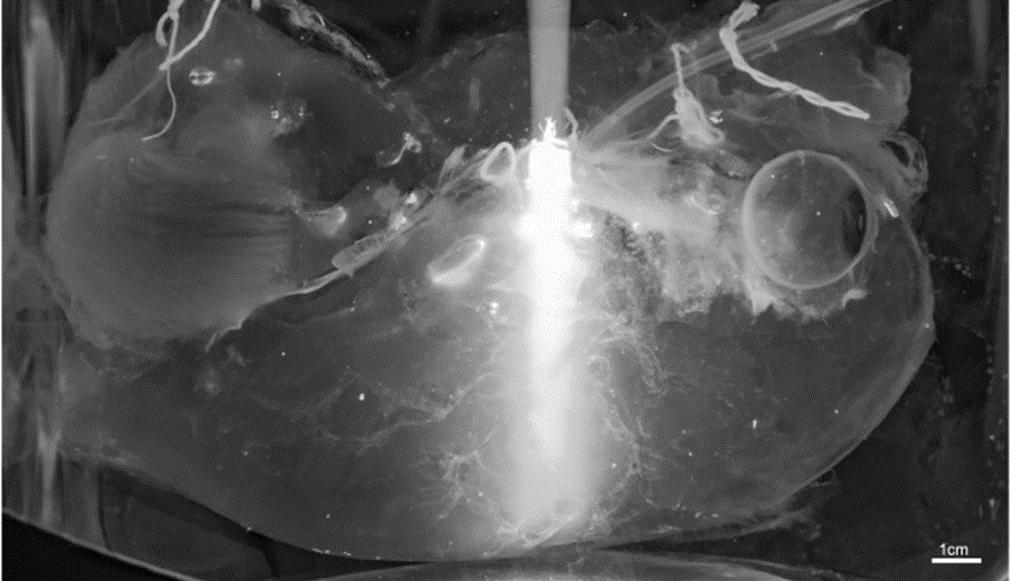

为了验证CHAPS的穿透效果,研究首先在猪脑上开展了实验。实验人员将一颗12.0×7.3×5.0cm大小的成年猪脑用CHAPS透化、N-甲基二乙醇胺(NMDEA)脱色、乙醇脱水、二氯甲烷脱脂、苯甲醇与苯甲酸苄酯匹配折射率后,在一个半月的时间里就让富含髓鞘的白质、丘脑和脑干变得透明。

接下来,研究团队将目光转向了人脑。他们以人脑中的四根动脉为管道搭建起了一套压力泵循环系统,在清理血液残留并固定后,采用上述SHANEL方法透化。4个月后,经过短波红外成像、高强度白光透射和磁共振成像三重验证,该研究首次得到了一颗透明且完整的成人大脑。